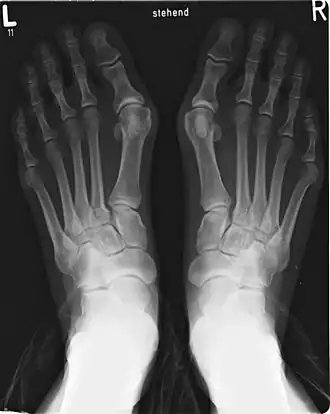

Esqueleto, articulaciones y ligamentos

Radiografía de un pie derecho en vista dorsal que muestra los huesos del dedo gordo. El ligamento de Lisfranc está situado en la marca roja de la esquina superior izquierda, y el borde inferior del dedo se destaca con una línea verde.

Anatómicamente forma parte de una cadena osteoarticular de tres piezas que prolonga el arco medial del pie partiendo de la primera cuña, el llamado «primer radio plantar». Sus componentes óseos parten del primer metatarsiano, y cuenta con solo dos falanges—siendo la falange media o segunda falange la que está ausente—[13]​ unidas mediante una articulación en pivote o trocoide, en tanto que el resto de dedos cuentan con tres. En la conexión metatarsiano-falange se encuentra el sistema glenosesamoideo, del que no disponen el resto de los dedos, y que está formado por dos huesos sesamoideos, que actúan a modo de polea (mecanismo sesamoideo) ayudando a los tendones de los músculos del dedo gordo en su función.[14]​ El sistema está formado por el cartílago glenoideo, que amplía la cavidad articular de la falange, y los dos huesos sesamoideos unidos por el ligamento intersesamoideo.[15]

También encontramos el ligamento de Lisfranc entre la base de la primera cuña y la cara interna de la base del segundo metatarsiano. Todos los dedos del pie poseen ligamentos intermetatarsianos que unen sus bases, salvo el dedo gordo con el segundo, el cual solo está unido a la cuña. Esto permite individualizar los desplazamientos, que en el resto de los dedos suceden en bloque debido a los ligamentos intermetatarsianos.[16]